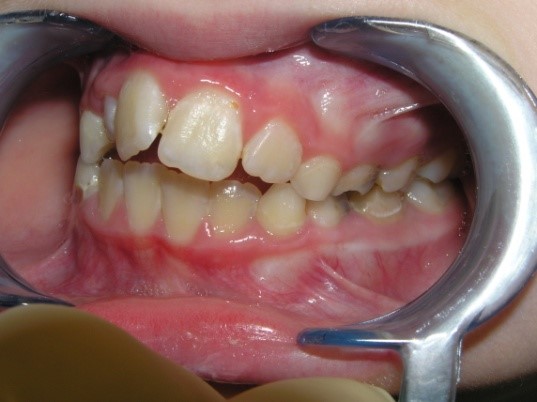

Pic.22. Tortoocclusion of teeth 11 and 21, open bite.

Pic.23. Tortoocclusion of teeth 11 and 21, prognathic, cross bite.